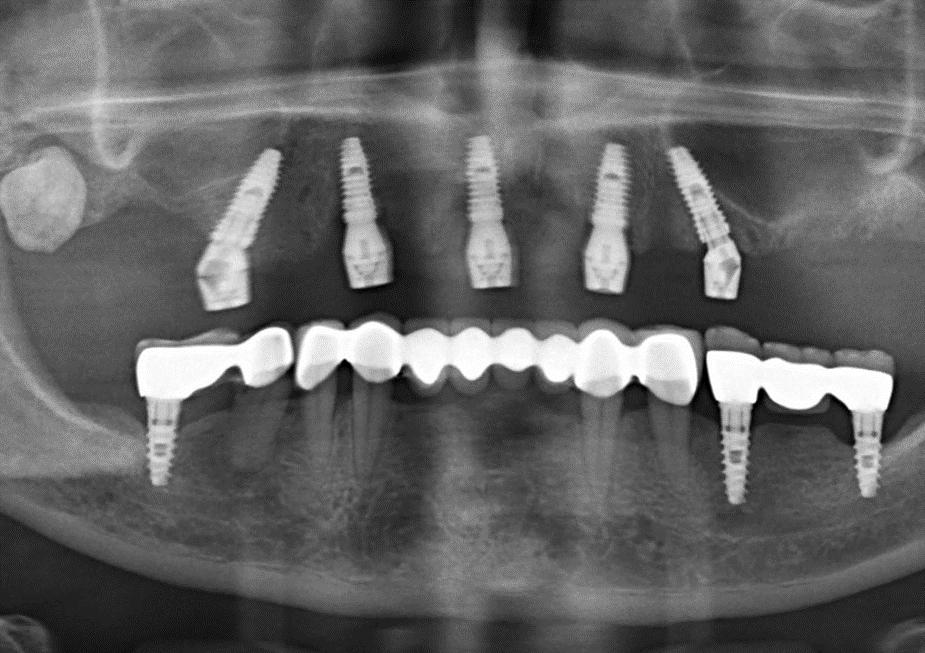

Cerrahi & Protez

• Kılavuzlu yerleştirme

• Post-op kontrol